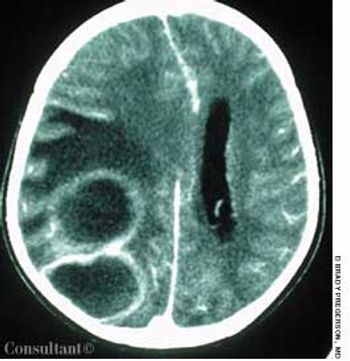

A 60-year-old comatose man was brought to the emergency department (ED). He had a history of diabetes, hypertension, and alcohol abuse. Relatives reported that the patient was noncompliant with his antihypertensive medication regimen.